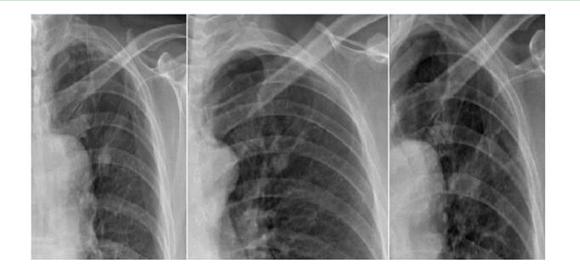

案例一:

第一年 第二年 第三年

案例解析:

在該案例中,病患在單一胸片檢查中,診斷出左上肺高密度結節(jié)影,前兩次在胸片攝影檢查得出的診斷結果并無大礙。相隔一年再去復查被誤診為“結核硬結灶”,并針對此而治療。但是,到了第三年之后,再次診斷發(fā)現(xiàn)結節(jié)影明顯增大,后才被確診為是肺癌,但為時已晚;如使用具備可視化點片功能的DR設備,胸片與胸透無縫結合,在透視下對“高密度結節(jié)影”全方位、多角度的高清點片獲取更多的確診信息,進一步病理分析,第一時間得出確診結果,做到早發(fā)現(xiàn)、早治療,結果將會截然不同。